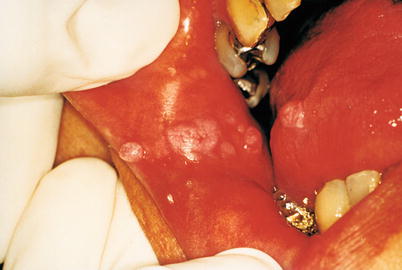

Fig. 9.48

Eight-year-old indigenous with multiple HPV lesions in the oral cavity. Some small, on lips, and other larger (see photo) on the buccal mucosa. This is a case of focal epithelial hyperplasia, also known as Heck’s disease. This is a benign disease and more commonly found in indigenous populations, among the natives of the State of Roraima, Brazil. It is correlated with human Papillomavirus types 13 and 32